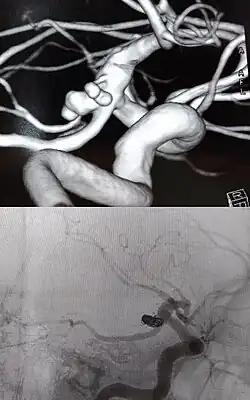

Existem duas formas básicas de tratamento: por microcirurgia (clipagem) e por via endovascular.

Tratamento por Via Endovascular

O tratamento por embolização dos aneurismas cerebrais começa com a inserção de um cateter (pequeno tubo plástico) na raiz da coxa, na artéria femoral na perna do paciente e navegação dele pelos vasos arteriais, passando pela pelva, abdômen, tórax, pescoço e base do crânio até o aneurisma. Através desta viagem pelo corpo, retificadas pelo cateter, pequenas molas ou espirais de platina são inseridas aos poucos dentro do aneurisma. O processo é assistido por meio de imagens radiológicas, visualizadas em um monitor de vídeo. Ao serem destacadas do cateter são desdobradas dentro da luz no aneurisma, ocupando aos poucos o interior, interferindo no fluxo de sangue para o interior do aneurisma, causando coagulação da luz, redução da pressão interna provocada pela pressão sanguínea e prevenindo sua ruptura. As molas são feitas de platina para que eles possam ser visíveis pelo raio x e bastante flexíveis para conformar-se com a forma de aneurisma e tentar evitar que ele se rompa. Um grande número de pacientes no mundo inteiro já foram tratados com molas de platina destacáveis. As micro-molas mais utilizadas para a embolização do aneurisma são as molas destacáveis de Guglielmi.

Os médicos, preferencialmente neurorradiologistas experientes em intervenções por angiografia encefálica, usam a tecnologia de raios-X em tempo real, chamada visualização fluoroscópica (radioscopia), para visualizar o interior dos vasos sanguíneos. As características externas do aneurisma apenas podem ser visibilizadas pela cirurgia aberta.

Há risco de óbito por nova hemorragia desencadeada durante a intervenção pelo próprio método, enquanto são inseridas as molas metálicas dentro da lesão aneurismática. Pacientes que sobrevivem às complicações podem ter lesões neurológicas permanentes. Há também o risco de recanalização (reformação do aneurisma) ao longo dos anos seguintes, pois a abertura natural da base do aneurisma, por onde são inseridas as molas, pode permanecer aberta, apesar da formação do coágulo misturada às molas destacadas dentro da luz aneurismática e a sua não visualização do aneurisma nas angiografias posteriores de controle.

Outra técnica endovascular para tratamento de aneurismas cerebrais é a utilização de stent diversor de fluxo, como uma alternativa para a embolização, embora as técnicas possam ser combinadas, especialmente em aneurismas grandes/gigantes.[5][6] É principalmente eficaz em aneurisma sacular não roto de colo largo, que são difíceis de embolizar devido à tendência (conhecida como prolapso) das molas preencherem a artéria-mãe. Outra situação é a forma fusiforme ou circunferencial dos aneurismas. Antes dos diversores de fluxo, muitos aneurismas intracranianos não podiam ser tratados.